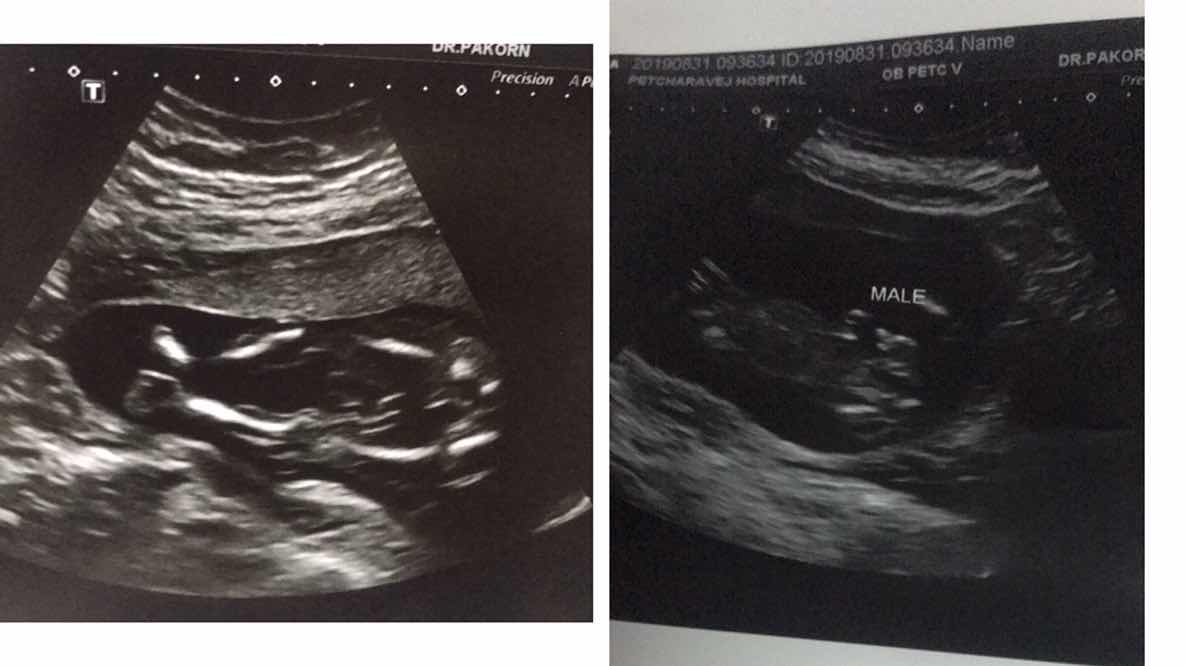

5เดือนคับผม

5เดือนคะผู้ ช

ตอน5เดือนค้า